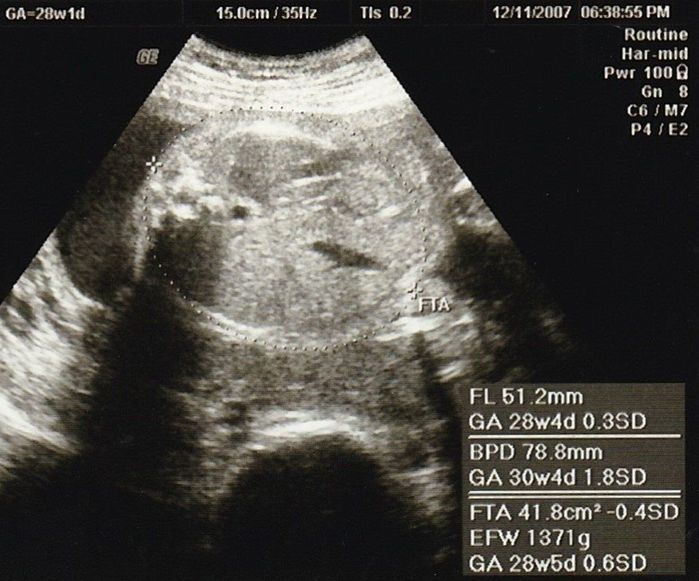

妊娠28週目のエコー写真

この辺から、少し動くだけで息切れするようになり、寝ても起きても息苦しさを感じていました。思ったより体力がなくなり、マタニティーヨガに通ったり、胎教にとクラシックや童謡や英語の曲などを聴いたりして気分転換を心がけて過ごしました。